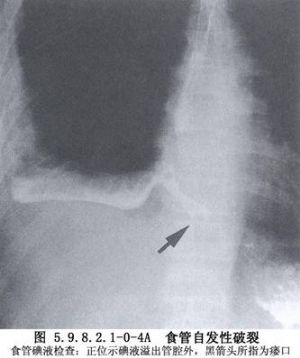

食管穿孔的早期診斷存在一定困難,在合併嚴重複雜損傷的情況下,其症狀及體徵往往被掩蓋。因此,在食管可能受到損傷的情況下,如果發現頸部、胸部皮下氣腫,應高度警惕食管穿孔的發生,此時X線檢查常有助於診斷。頸部食管穿孔,X線攝片早期即可發現頸部筋膜層有遊離氣體。若已形成膿腫則可出現局部緻密陰影,其中可有氣液麪。胸部食管穿孔,X線檢查可見縱隔積氣或縱隔影增寬,一側或雙側液氣胸。左側液氣胸常爲低位食管穿孔,右側液氣胸多爲中段食管穿孔。食管造影不僅可明確診斷,而且還能確定破裂部位、範圍及穿孔方向。胸腔穿刺抽出液呈酸性,pH<6,應考慮下段食管穿孔。口服亞甲藍溶液,胸腔穿刺抽出液呈藍色,可以確診食管穿孔(圖5.9.8.2.1-0-4~5.9.8.2.1-0-7)。